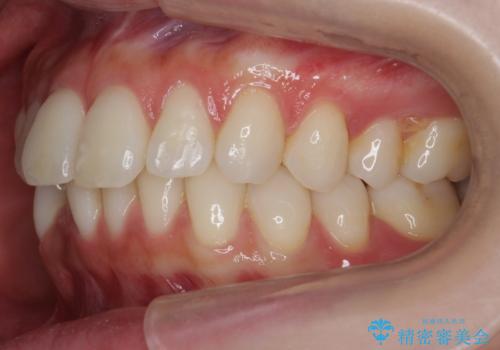

昔ワイヤー矯正をして後戻りした 軽度のがたつき モニター矯正

- 矯正治療後の後戻りを主訴に来院。

特に下の前歯のがたつきを気にされていました。

マウスピース矯正で再矯正を行いました。

再度の後戻りを防ぐため、下顎前歯の裏にはワイヤーを貼る保定を行っています。